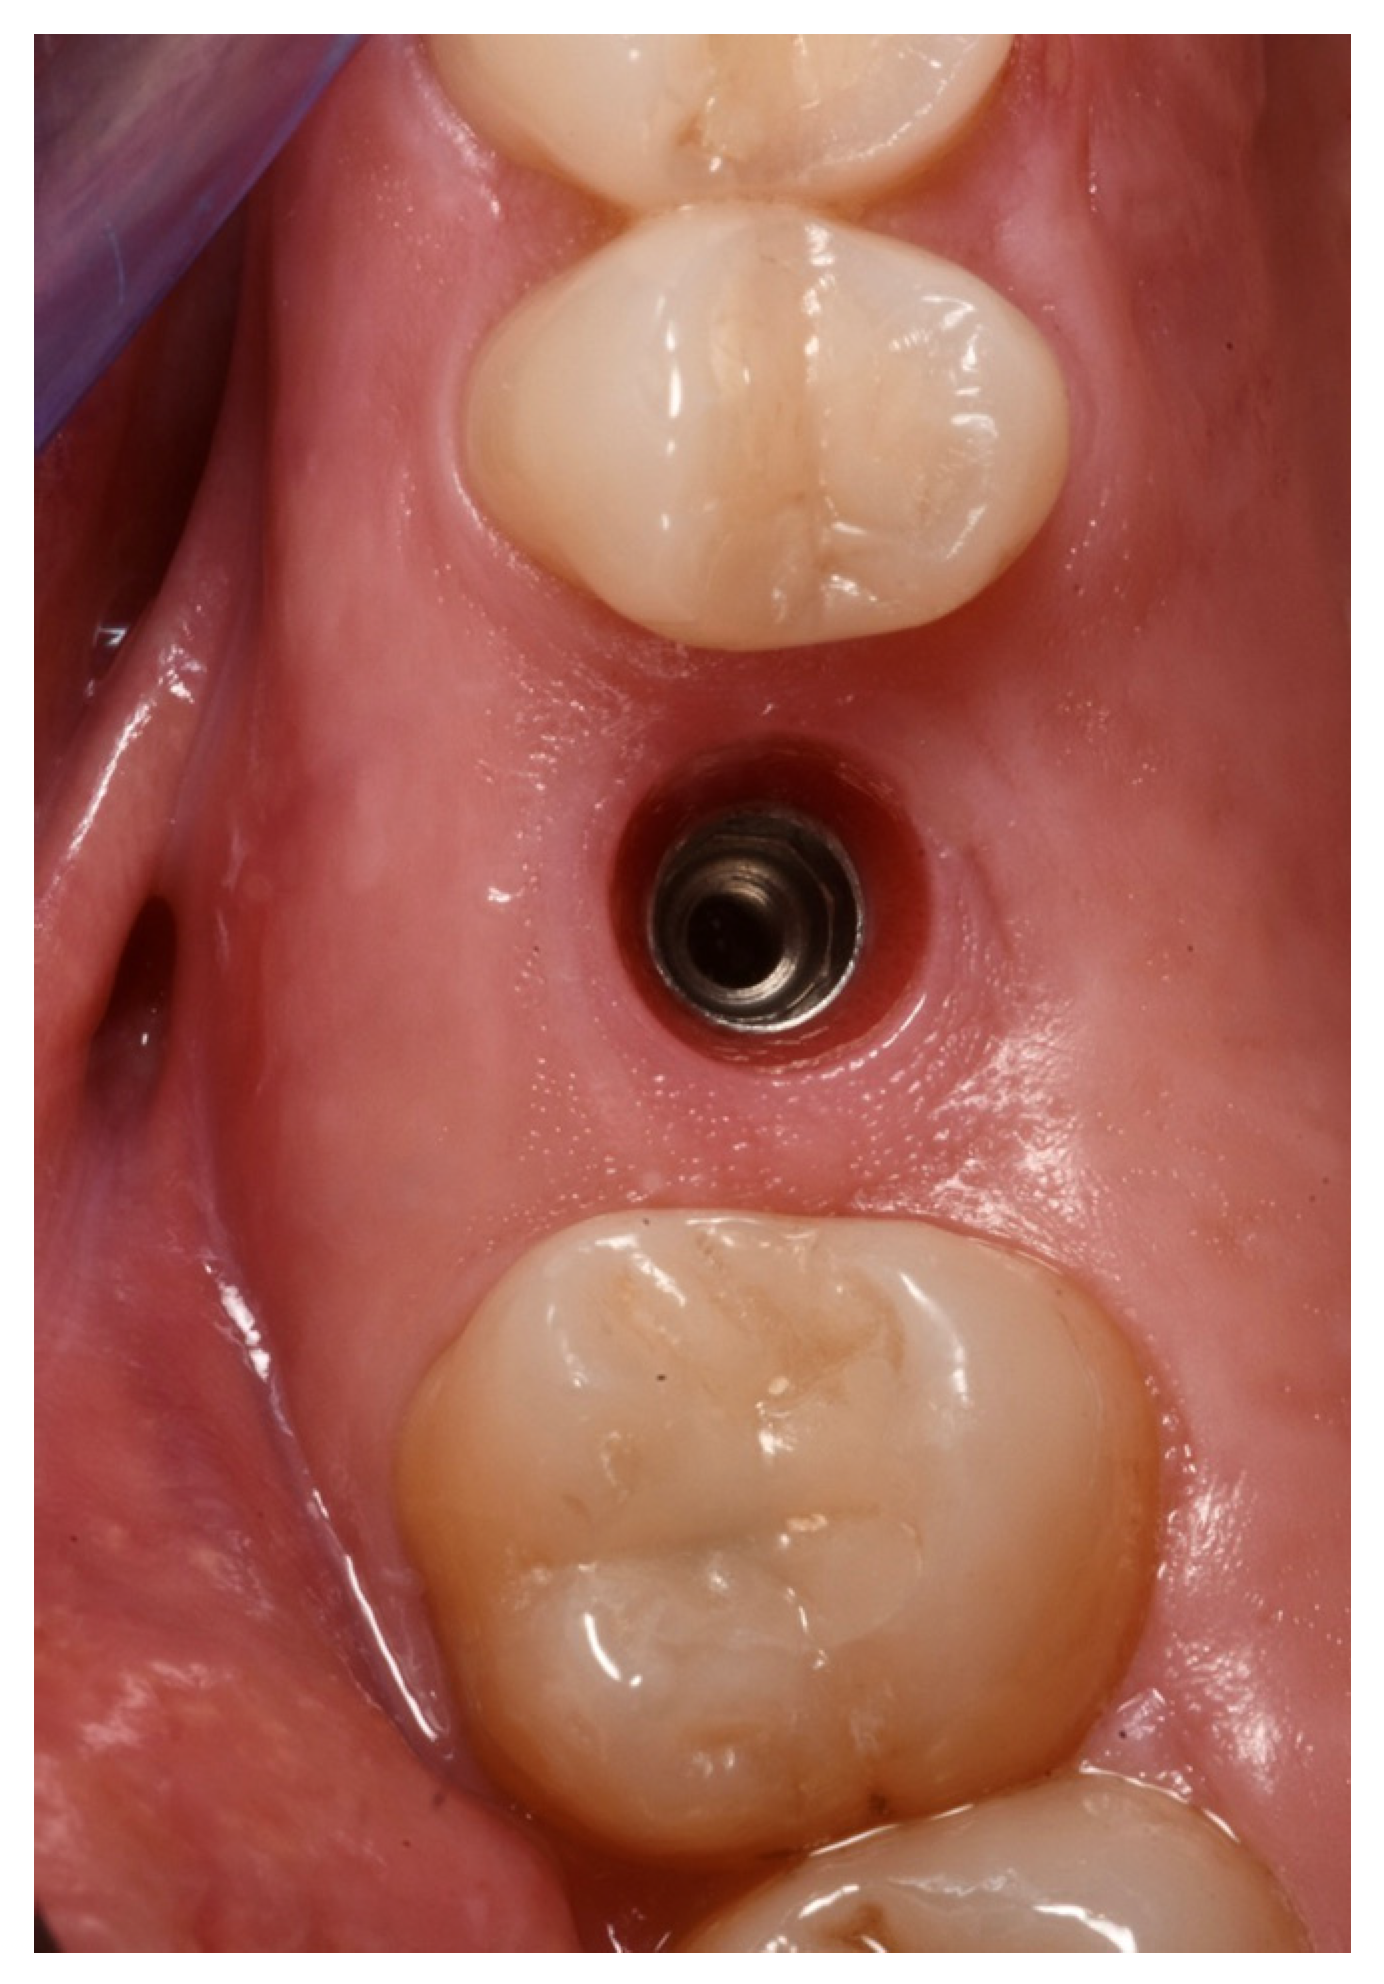

2.6. Case Presentation. Nano-HA Applied to Socket Preservation Procedures

3. Results